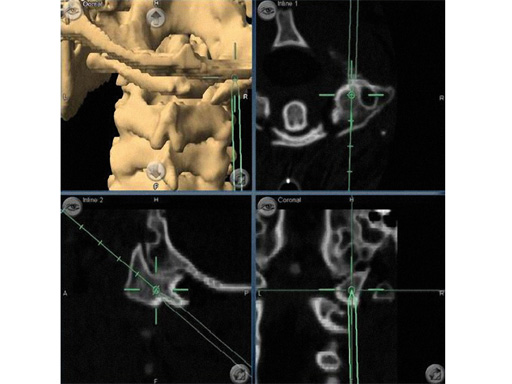

The most basic imaging for spinal surgery consists of static AP and lateral x-rays or image intensification during surgery. In CAS a virtual representation of the surgeons instruments are shown in relation to the patients anatomy that is displayed on a separate computer screen. CT scans or image intensifier images are used to generate the virtual surgical reality. This surgical GPS requires the attachment of a reference array with reflective beads to the patients spinal anatomy and to the surgical instrument to be tracked. The 2-D information obtained by two infrared cameras tracking these beads is converted into a 3-D representation based on the different reflective angles (Fig 1). Tracking using electromagnetic instead of infrared technology is currently being evaluated and has shown promising results [6, 7].

Intraoperative CT scans can be obtained using image-intensification- based isocentric C-arms, portable cone beam CT (O-arm, Medtronic) or true intraoperative CT scanners (iCT). Isocentric C-arms and portable scanners offer the advantage that they can also be used as regular C-arms, however their imaging quality may be inferior to stationary CT scans (Fig 3).

Fig 3ac a Intraoperative CT scans from an image-intensification-based isocentric C-arm. The software allows simulation of various diameter and length screws. bc Comparison of intraoperative simulation and postoperative CT scan shows the high accuracy of CAS.